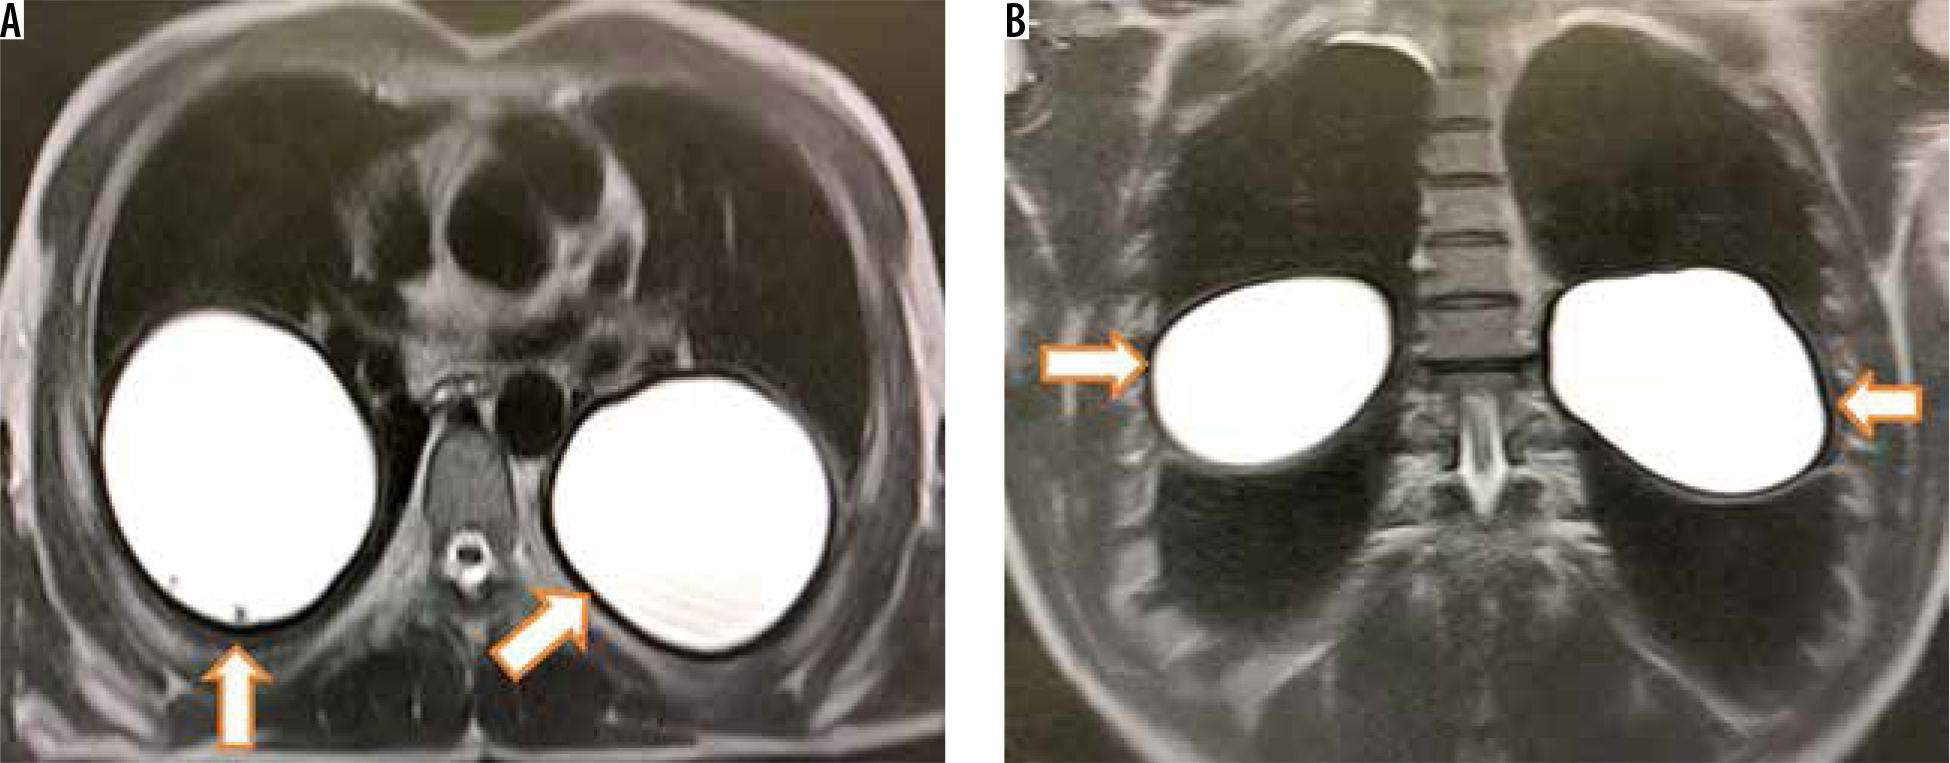

Among the total study population 41 patients were evaluated with T2-weighted MRI of the thorax. T2-weighted MRI showed hyperintense cyst with hypointense rim in 11 cases (Figure 5) whereas 19 cases showed hyperintense cystic lesion with internal floating wavy hypointense membrane (Figure 6). Based on the classical findings of hyperintense pulmonary cystic lesion with T2-weighted hypointense rim or detached internal T2-weighted hypointense membrane, a correct diagnosis of hydatid cyst was possible in 30 patients (true positives) whereas a correct alternate diagnosis was made in 8 cases (true negatives). T2-weighted hyperintense cyst with presence of hypointense rim helped diagnose 11 patients whereas hyperintense cyst with presence of folded or floating wavy T2-weighted membrane aided the diagnosis in 19 ruptured cysts. These two findings together diagnosed 30 (90.9%) hydatid cysts correctly (true positives). However, 2 (6%) cysts were wrongly classified as hydatid cysts based on these findings (false positives). One was found to have fungal abscess and another proved to be schwannoma (Figure 7). One case with absence of T2-weighted hypointense rim was finally proven to have hydatid cyst (false positive) (Figure 8). Eight patients with presence of thick wall with absence of hypointense rim or floating wavy hypointense membranes or cyst with solid cystic composition were given an alternate diagnosis (true negatives), and biopsy was suggested. Details of patients who underwent additional MRI are given in Table 2. Among the true negatives, necrotic lung carcinoma was found in 3, cystic metastasis in 1, abscess in 3, and bronchogenic cyst in 1 patient. Two patients with intravascular filling defects in pulmonary arteries on CT were found to have intravascular T2-weighted hyperintense cysts (Figure 4E) or tubular hyperintense intravascular cyst (Figure 4F).

Figure 5

Axial (A) and coronal (B) T2-W magnetic resonance imaging shows two homogeneously hyperintense cysts with smooth peripheral hypointense rim in both lungs